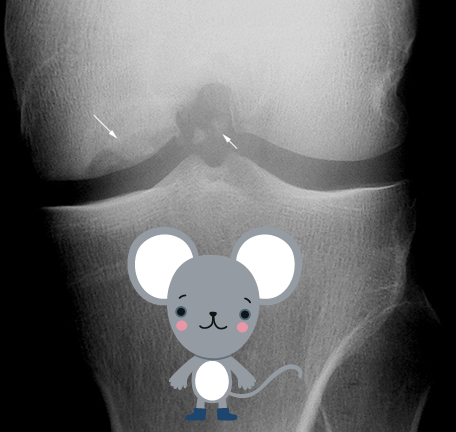

Small fragments of subchondral bone necrotize if displaced, undisplaced frags may reattach and revascularize

frags are known as “joint mice”

high incidence in medial condyle 75%

Osteochondritis Dissecans - Radiographic Appearance

cartilage fragments are only seen on CT, MRI, NM

aim is to assess location of frag within joint space and origin

requires tunnel/notch view for best assessment